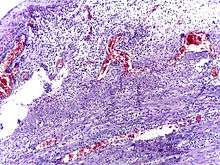

Pathology

The definitive diagnosis is based on pathology. The histologic finding of appendicitis is neutrophilic infiltrate of the muscularis propria.

Periappendicits, inflammation of tissues around the appendix, is often found in conjunction with other abdominal pathology.[56]